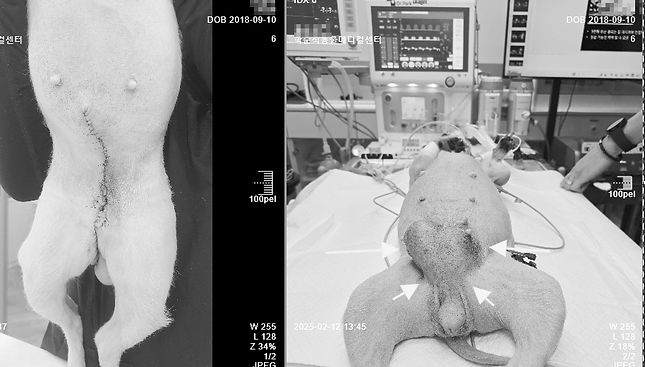

잠복고환수술

개와 고양이 수컷은 행후 5개월 전후 성숙이 이루어지기 전에 양측 고환을 제거하는 중성화수술이 필요합니다.

수술은 간단합니다. 하지만, 고환이 복강내 잠복되어 있는 경우 복강 절개를 통한 잠복고환적출 수술이 필요합니다.